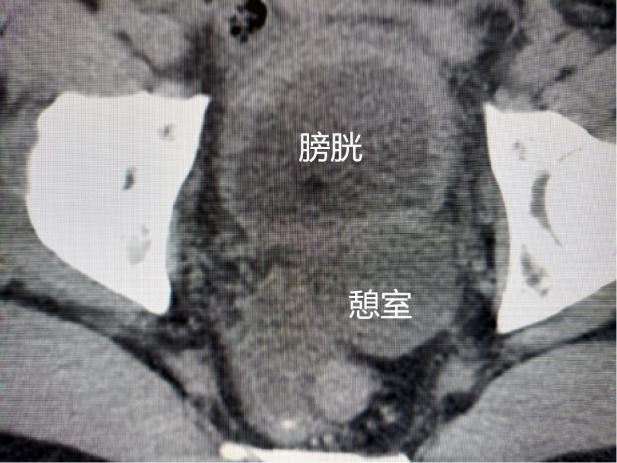

63岁的罗大叔自2年前出现尿频、尿急的情况,每天夜里至少起床排尿2-3次,罗大叔认为年纪大“前列腺增生”很正常,并未在意也没及时就医治疗。近段时间症状加重排尿困难并伴有尿痛、血尿,来到我院泌尿外科门诊找到齐正华主任,经详细问诊,安排其住院治疗,入院后完善CT提示:前列腺增生合并膀胱巨大憩室。

经泌尿外科团队讨论后,决定为患者施行腹腔镜下膀胱巨大憩室切除术,手术顺利。术后拔除尿管后,罗大叔排尿通畅、症状消失,非常满意。出院时罗大叔高兴的说:“我以为要开大刀,没想到几个小孔就解决了,你们的技术真的好!” 术前影像 术后影像 切下来的膀胱憩室 微创小孔 科普知识 什么是膀胱憩室?它有什么危害吗? 膀胱憩室主要是由于患者膀胱肌肉先天性的薄弱,或者是由于尿路梗阻导致的膀胱内压的升高,最终在膀胱壁表面形成了一个膀胱黏膜经膀胱壁肌层向外膨出的囊袋,就好像是多了一个膀胱一样。如果憩室较小,可无明显症状。但如果憩室较大,则会出现排尿困难、尿频、尿急、尿痛、血尿以及两段排尿等相关症状,严重时可出现严重的并发症。 并发症: 1.便秘-膀胱憩室压迫到了患者的直肠,从而导致患者出现便秘。 2.难产-巨大的膀胱憩室压迫到子宫,导致女性患者难产。 3.憩室感染、憩室结石-患者可出现尿频、尿急、尿痛等尿路感染的症状,严重者甚至并发憩室结石。 4.尿路梗阻-憩室增大可以压迫输尿管使之产生位移,从而出现梗阻。 5.肾功能不全或者肾衰竭-当患者的憩室增大导致出现尿路梗阻,如梗阻进一步发展,使得肾小囊内压力增高造成肾小球率过滤的降低,尿量减少,肌酐、尿素氮排出受阻,严重者可以出现肾功能不全或者肾功能衰竭。 6.尿潴留-膀胱憩室压迫膀胱出口,出现尿潴留。 7.癌变-膀胱憩室易合并有癌变,患者可表现为无痛性肉眼血尿。 合江县人民医院泌尿外科近年来大力发展腹腔镜技术,目前能开展的腹腔镜技术有:腹腔镜下肾癌根治术、腹腔镜肾盂癌根治术,腹腔镜无功能肾切除术,腹腔镜肾上腺肿瘤切除术,腹腔镜肾囊肿去顶减压术、腹腔镜前列腺癌根治术、腹腔镜膀胱全切术、腹腔镜精索静脉曲张高位结扎术,腹腔镜下输尿管切开取石术,腹腔镜输尿管狭窄切除吻合术,腹腔镜输尿管膀胱再植术等。 泌尿外科专科门诊:门诊综合楼二楼212诊室。 特需专家门诊:每周四上午,门诊综合楼一楼113诊室。 泌尿外科住院部:住院综合大楼五楼。 咨询电话:0830-5266595